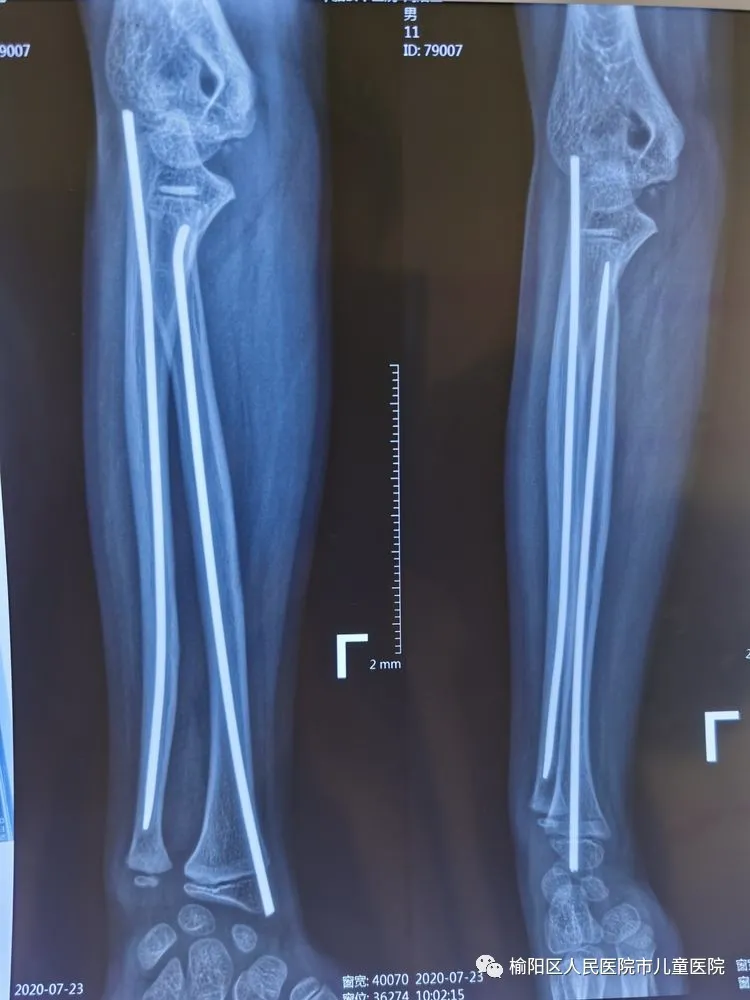

在全麻下行彈性髄內(nèi)針微創(chuàng)閉合治療

0.5cm的微創(chuàng)小口

術(shù)后5個月,完美愈合。